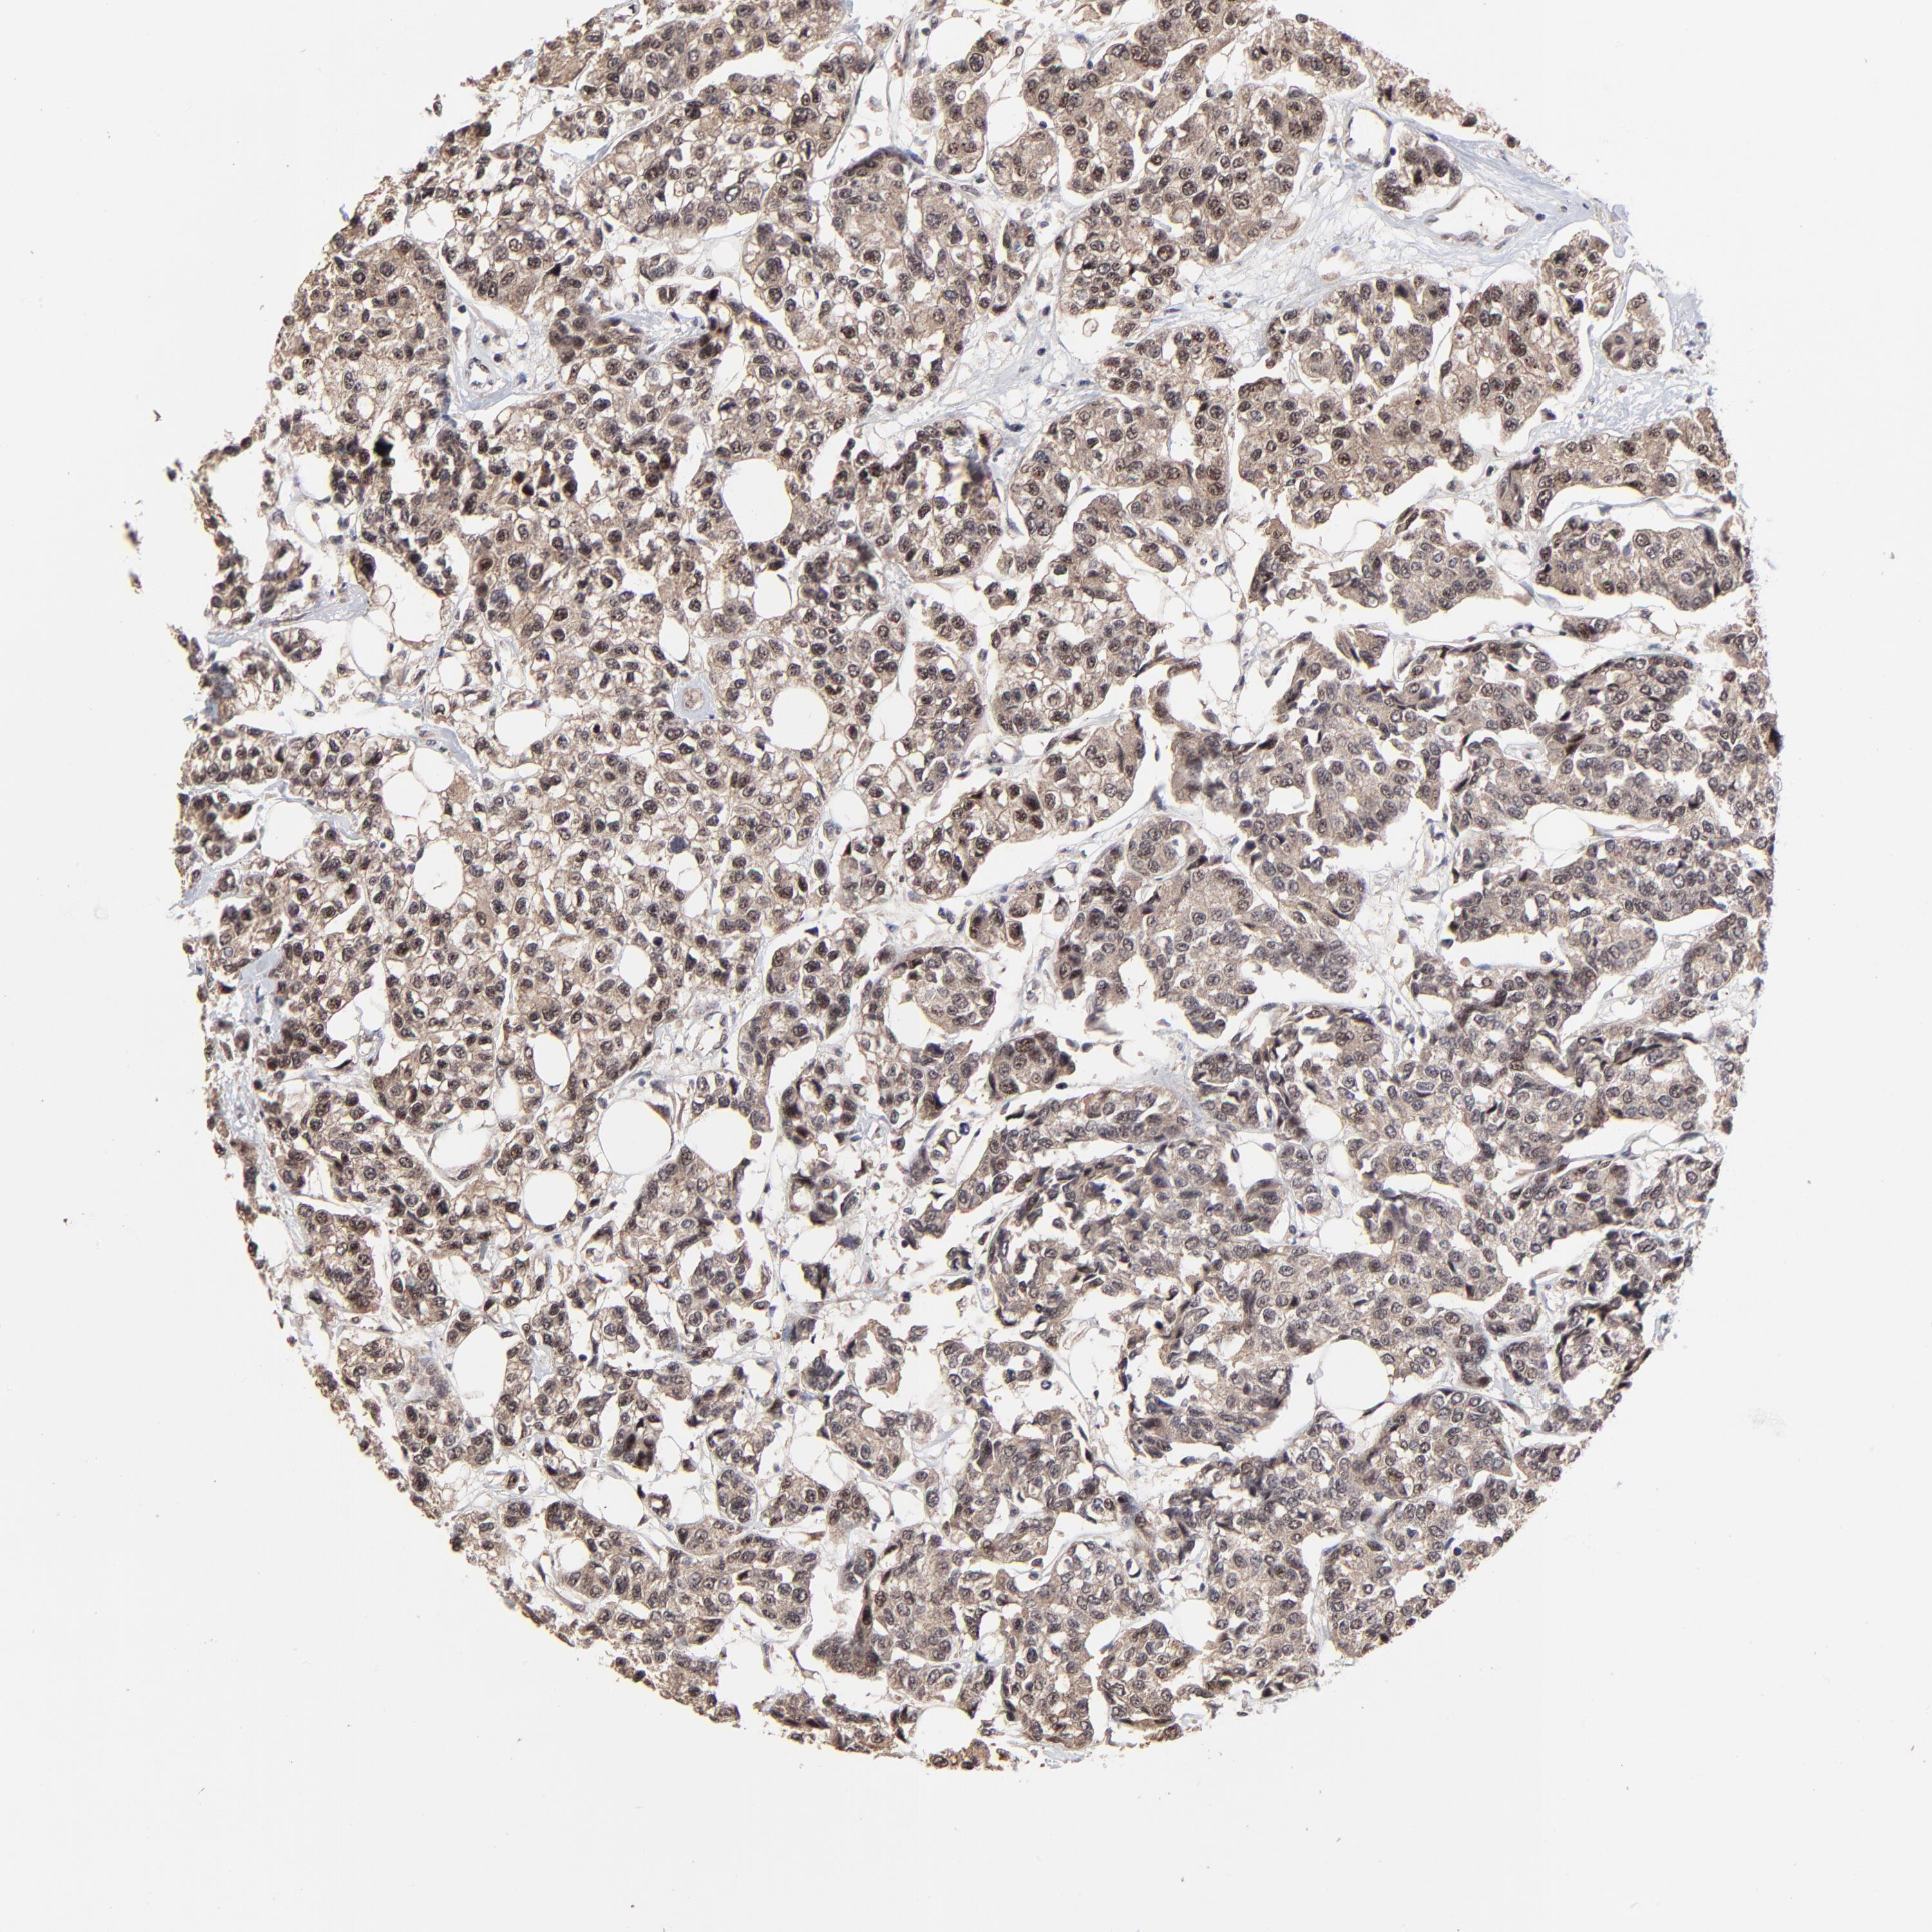

BRCA TCGA BRCA VALIDATION PROTEIN EXPRESSION